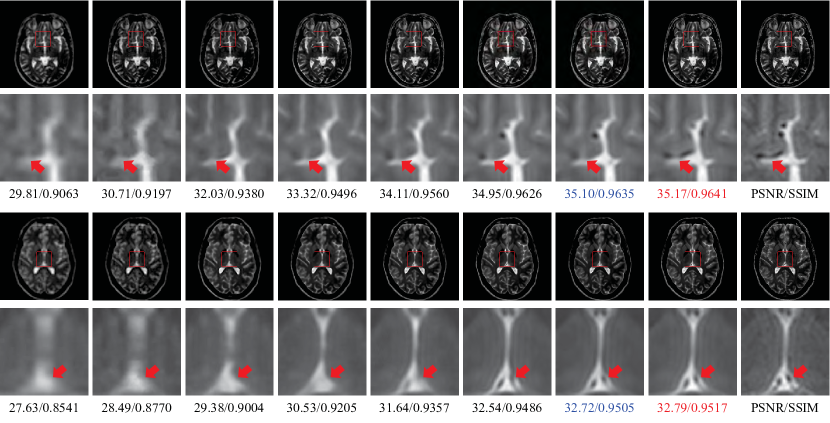

Figure 8: The visual comparison between several advanced SISR methods (truncation degradation) on T1 images with r=3𝑟3r=3 (top) and r=4𝑟4r=4 (bottom). The first to the last columns are Bicubic, NLM [62], SRCNN [21], VDSR [25], RDN [30], CSN [18], CSSFN-B4, CSSFN-B2 and the ground truth. The maximal PSNR (dB) and SSIM for each row are marked in red, and the second ones are in blue.

Visually, we can more easily observe the advantages of the proposed method to other methods. Fig.8 displays the visual effect of the compared methods on two T1 images with r=3𝑟3r=3 and r=4𝑟4r=4 respectively. The proposed method recovers images with clearer and sharper edges, thus making them more faithful to the ground truth. For example, there exists a dark line in the ground truth of the 2nd row of Fig.8 (indicated by the red arrow), but only the CSSFN-B2 gives a credible hint of this dark line. Fig.9 shows the results on two T2 images with r=3𝑟3r=3 and r=4𝑟4r=4 respectively. In this case, the visual advantage of our CSSFN model is more observable. The quantitative results below each image also confirm the conclusion.